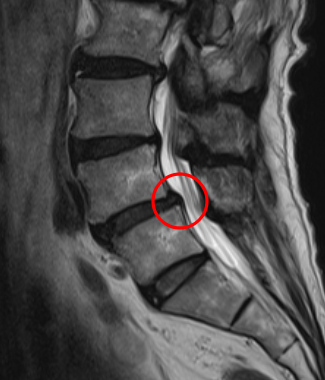

治療後

腰痛の原因を調べるため腰椎MRI画像を確認したところ、赤い枠内(L4/5)に椎間板ヘルニアが見つかりました。これが椎間板を圧迫して、腰痛が出てしまっていると考えられます。

術後から2週間後には腰痛が10点から5点へ軽減。このほか、こわばりや痛みも軽減したとのことです。また4ヶ月後にも経過観察を行ったところ、腰痛はさらに5点から2点に軽減し、終診となりました。